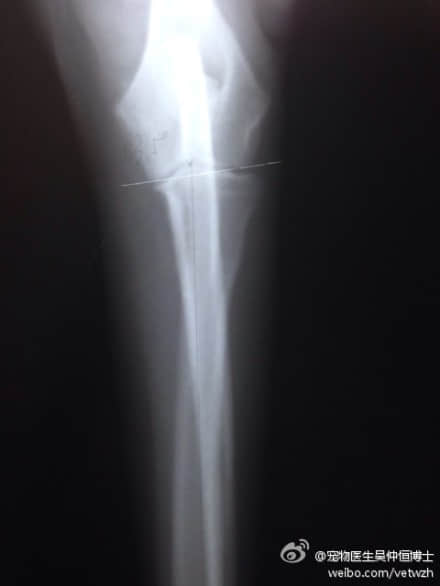

由于肘关节受力问题引起了一系列的症状和疾病,所以在诊断上也需要看肘关节受力的情况。一般传统拍摄x光片的方法是让狗狗的手在一定角度下去拍摄x光片,以观察狗狗肘关节的病变。但是这种方式不能反映出狗狗肘关节的受力情况。于是,我们SAO讲师团队,参考了最新的研究成果,开发并定制了一套使肱骨和桡骨在同一直线水平面上,让前肢受力的情况下拍摄x光片的专用保定工具。用保定工具或者特殊保定方法拍摄出来的x光片更能反应出肘关节的受力情况,为宠物医师临床上提供更好的依据。我们也可以根据肘关节肱骨内外髁与桡尺骨中垂线的受力情况测量出受力角度(正常犬在81.5度左右)。通过分析受力的情况,从而制定治疗方案。